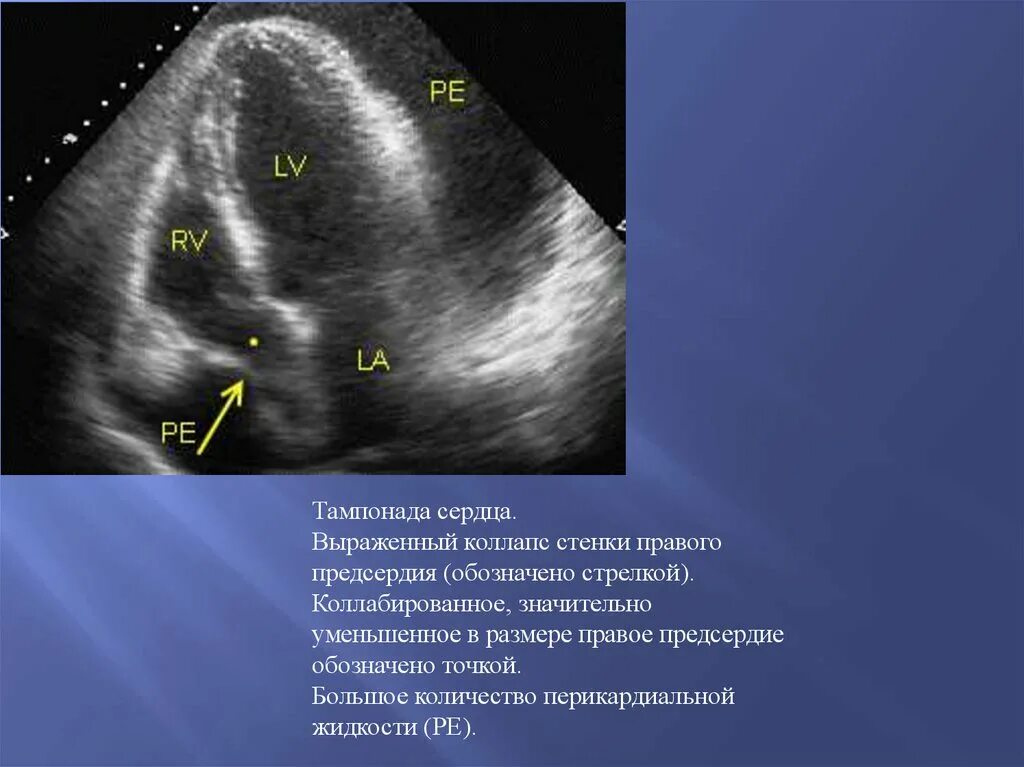

Коллабирование это